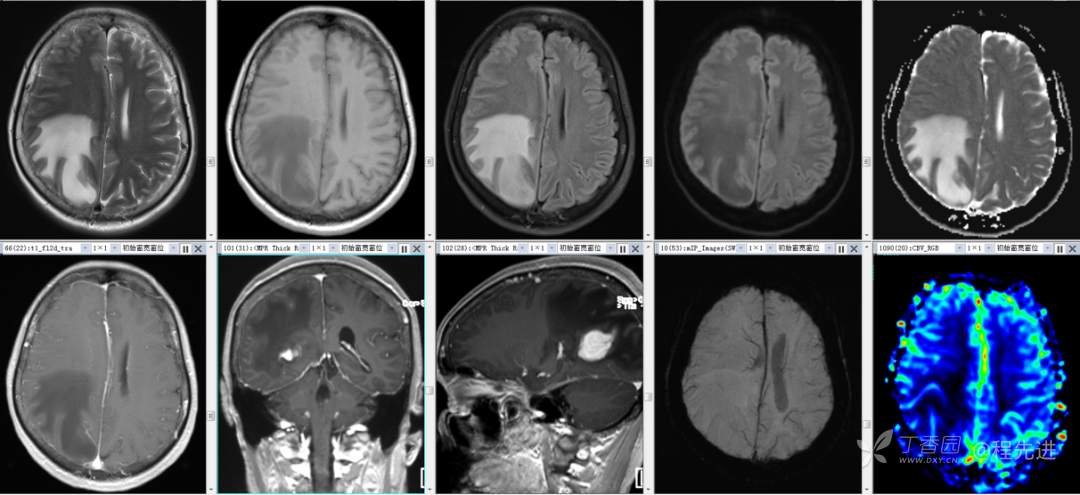

辅助检查:外院头颅 CT 示:右侧顶枕叶占位。

颅脑 MRI 平扫+增强: